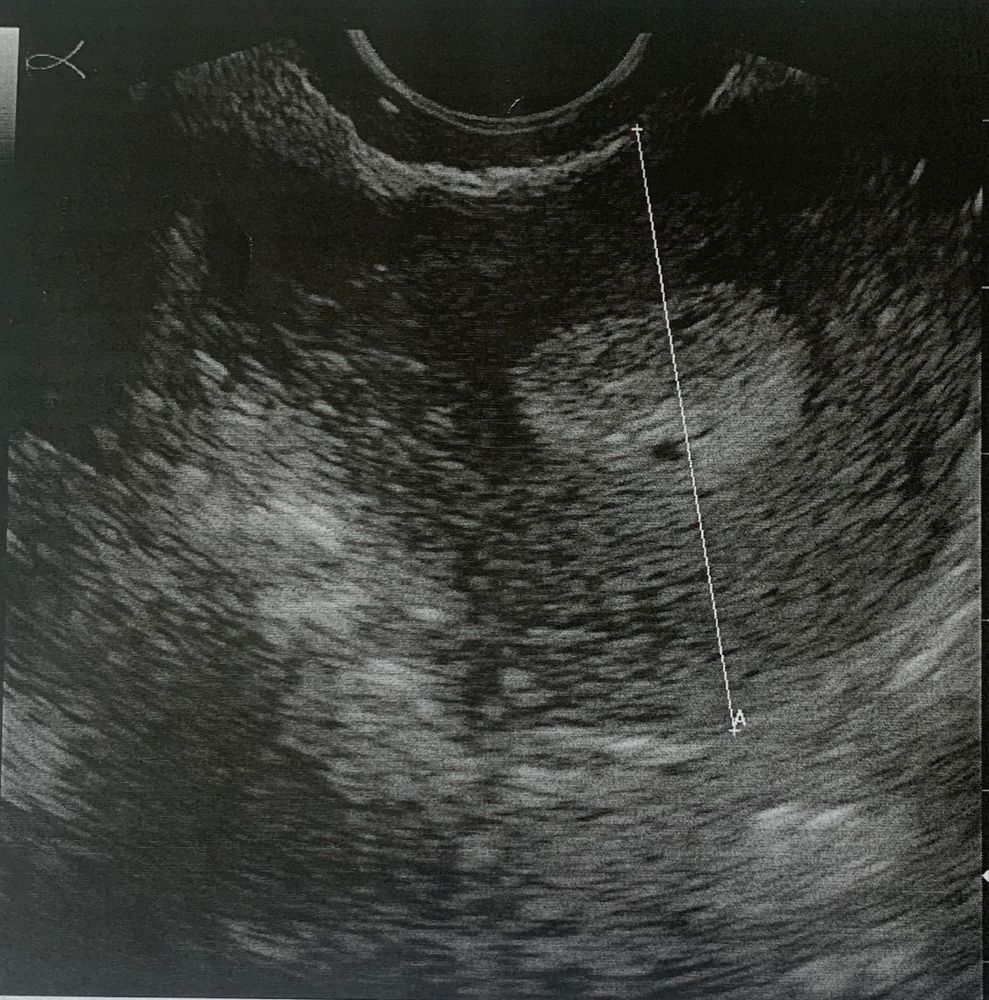

Имплантация без ХГЧ и без беременности

Здравствуйте, сразу скажу вам я врач, врач УЗИ. То что на фото это не кисты в эндометрии, а полости жидкостные, встречаются часто перед месячными прям за пару дней, можно принять за беременность малого срока конечно, но ХГЧ уже должен быть более 600 ЕД, но эндометрий в 18 мм это не норма, а эти самые полости ещё раз это подтверждают (возможно воспалительные)! Какая бы поддержка не была более 16 это гиперплазия, и имплантации у вас не было. Ни о каких субмукозных узлах тут речи не идёт (судя по фото) не слушайте местных экспертов :) я бы проверяла эндометрий точно. И скажите на какую толщину переносили?

Шепокляк_, здесь на фото одна видна, вторая меньше, выше и левее, но ее здесь не видно Изображение

Kate Agaeva, я не знаю 🙈 гинеколог это назвала беременностью, а вот фотка с узи Ре сегодня (там обе видно), он говорит что то что на фото, свидетельствует о том что была имплантация, у меня уже мозг кипит🤯. Также говорит что это выйдет вместе с месячными. а те кисты о которых вы говорите, могут быть из-за процедуры эко в целом? У меня ничего подобного никогда не было Изображение

LeLu, Очень похоже на субмукозный узел

LeLu, Забейте: Субмукозный узел в сагитальной плоскости, очень похоже

вероника, забила, ни одной похожей на мое узи картинки Изображение